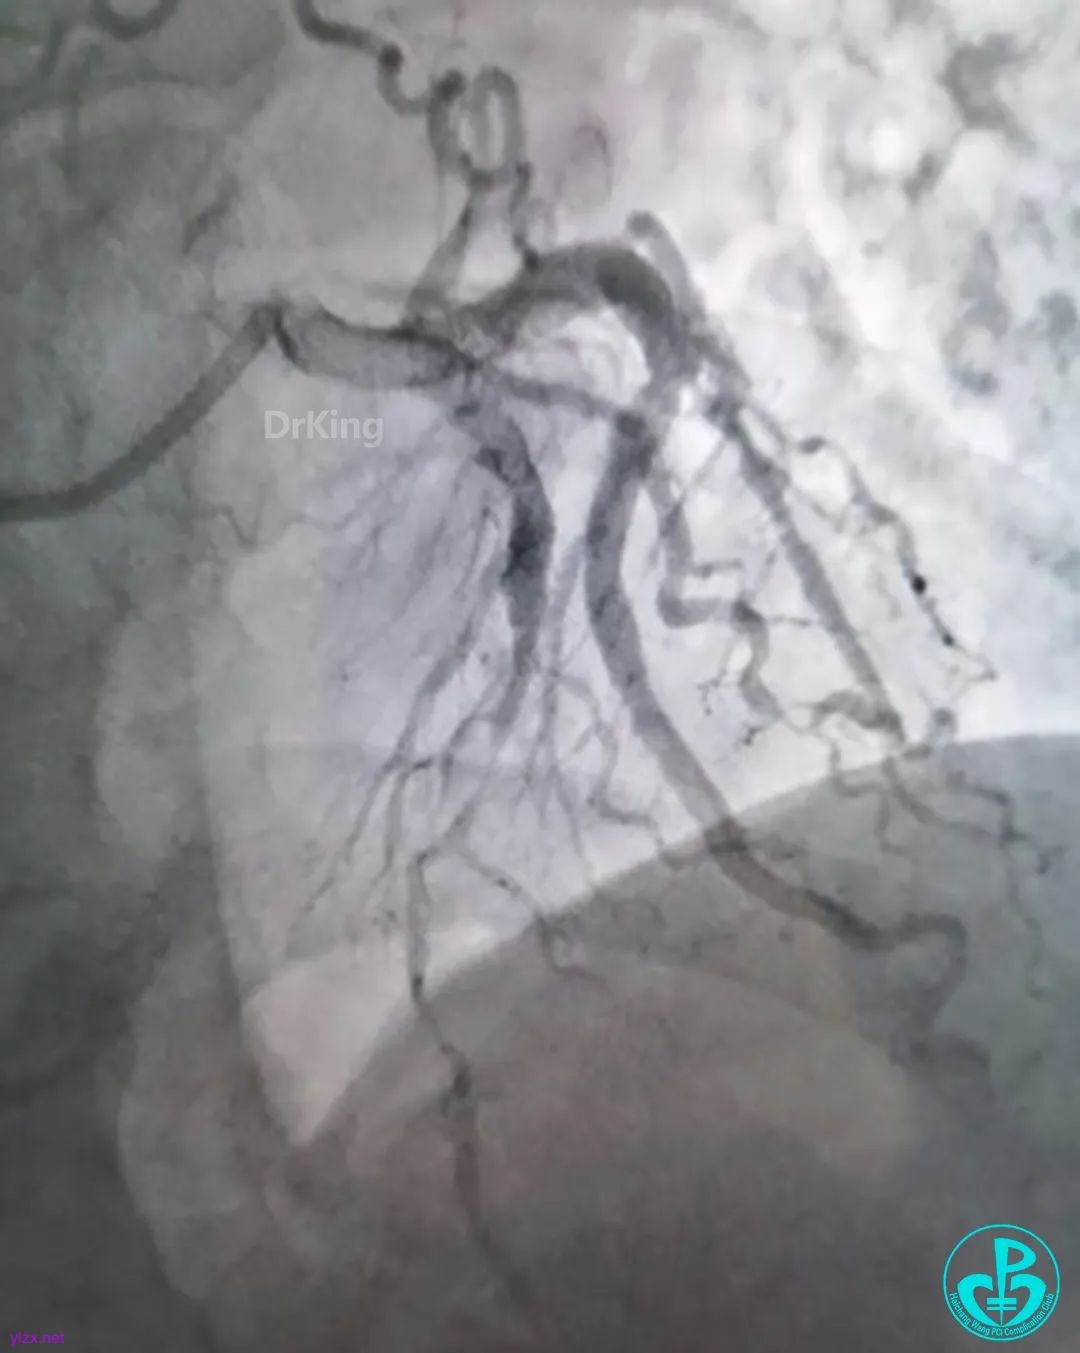

走左边,终于到位,造影。

左边EBU。